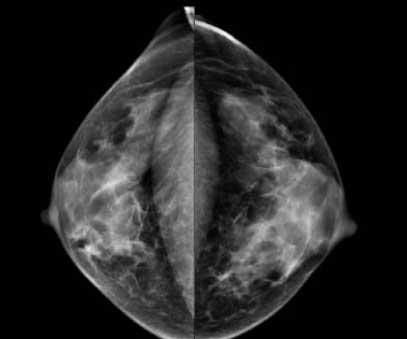

Recent studies have found that dense breast tissue is a strong independent risk factor for breast cancer. Breasts are composed of fat and fibroglandular tissue. Dense breast fibroglandular tissue appears white on a mammogram. Abnormalities and tumors also appear white on mammograms, causing them to be difficult to spot in dense breasts until the cancers are much larger and possibly in advanced stages.